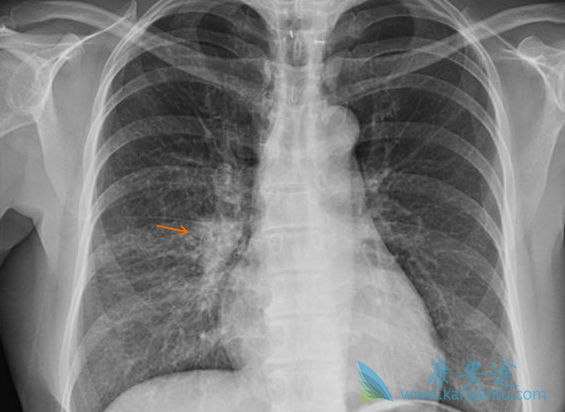

对于 EGFR 突变和 ALK 重排非小细胞肺癌(NSCLC),肺癌脑转移(BM)是诊断和复发时的第二常见部位。25%~50% NSCLC 在整个疾病过程中出现 BM。30%~60% EGFR 突变、40%~70% ALK+ 非小细胞肺癌患者发生 BM。

BM 影响生存期和生活质量,预期生存期(OS)3~15 个月。因药物很难透过血脑屏障(BBB),放疗是脑转移的治疗基石。对不适合手术或 SRS 的患者,一直以来全脑放疗(WBRT)作为首选。近年来靶向药物如酪氨酸激酶抑制剂(TKIs)对颅内病灶疗效显著,脑脊液(CSF)药物浓度增加。

单发或寡转移考虑局部治疗如 SRS,对 10 个以下脑转移 SRS 是安全的。不适合局部治疗的,保护海马区 WBRT 可减轻神经毒性。靶向治疗透过血脑屏障能力增强,显著改善 NSCLC 脑转移预后。对于驱动基因阳性患者,放疗联合靶向治疗策略可以用于处理颅内转移患者。免疫治疗对于肺癌脑转移有效,脑放疗联合免疫治疗的研究较少。